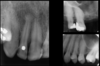

Define mesiodens

Supernumary tooth that develops on the maxillary midline

Describe the characteristics of mesiodens (6)

• Can prevent the eruption of central incisors

• Small tooth in a vertical, inverted or horizontal position

• Normal density of teeth

• Usually more palatal

• PDL space and lamina dura present

• Normal tooth architecture